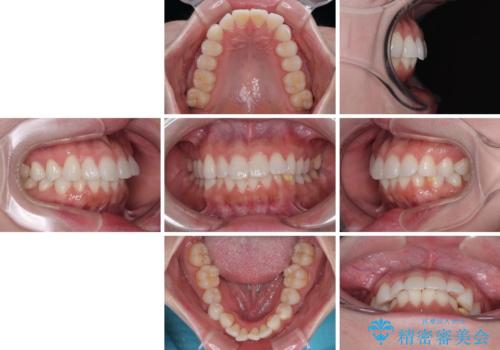

- 上下前歯の叢生を気にして来院された患者様です。

軽度な叢生であり、安価で短期間の治療を規模されていたため、インビザライン・モデレートを用いて矯正治療を行うこととしました。